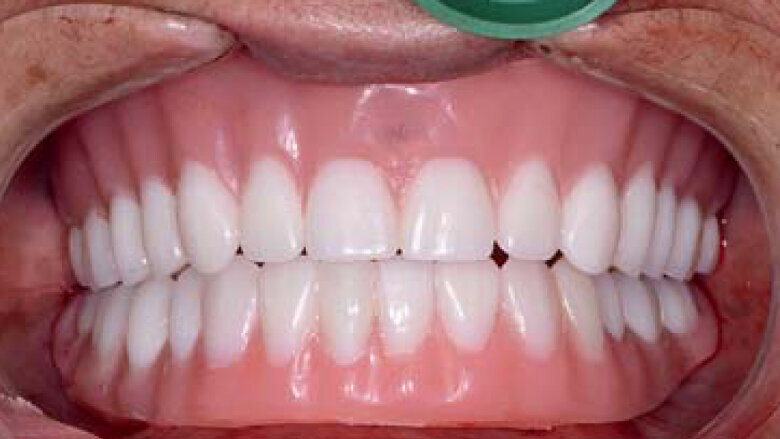

Une patiente dans la cinquantaine a consulté mon cabinet pour le traitement de son maxillaire édenté et de ses dents mandibulaires extrêmement déchaussées et cariées (Figs. 1 et 2). La patiente était une grande fumeuse, n’avait consulté aucun dentiste depuis plusieurs années, et négligeait de prendre soin de ses dents restantes en raison de l’inconfort et de la douleur qu’elle ressentait.

Fig 1 Vue préopératoire avec écarteur de lèvres

Les restaurations définitives ont été mises en place au cours de la visite suivante et montraient une adaptation, une fonction et une relation inter-occlusale précises (Figs. 21 et 22). Grâce à la phase d’essayage, aucun ajustement des prothèses en zircone monolithique n’a été nécessaire, car les bridges en PMMA avaient permis de définir précisément les modifications nécessaires à l’obtention de la forme et de l’esthétique parfaites. Une dernière radiographie a confirmé l’adaptation totale des restaurations en zircone BruxZir sur les piliers implantaires personnalisés Inclusive. La patiente s’est montrée extrêmement satisfaite de la reconstruction de ses arcades maxillaire et mandibulaire dont le rétablissement de l’esthétique et de la fonction dentaire lui avait rendu confort et confiance.